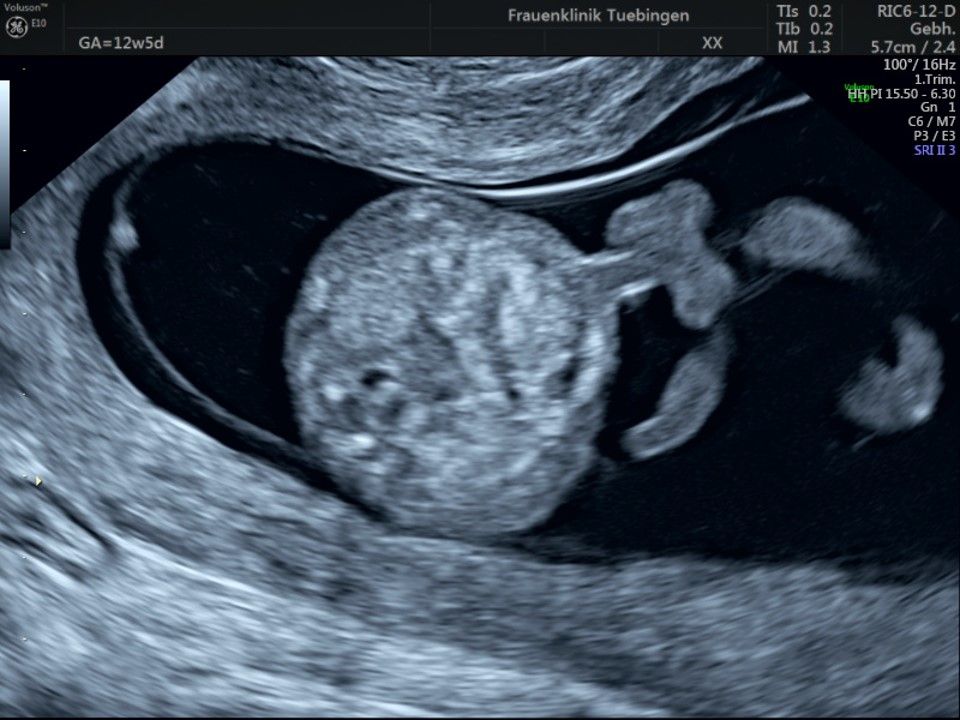

Bauchwanddefekt